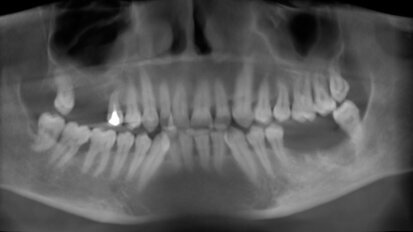

Terapia chirurgico-ortodontica di un canino mandibolare incluso

In letteratura, ci sono pochi studi sui canini mandibolari inclusi e sulle possibili soluzioni terapeutiche per il recupero in arcata. Il caso clinico ...